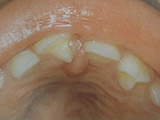

Τερηδόνα βρεφικής και νηπιακής ηλικίας ή τερηδόνα θηλασμού

Η τερηδόνα βρεφικής και νηπιακής ηλικίας εμφανίζεται σε μικρά παιδιά ηλικίας 2 έως 5 ετών, τα οποία έχουν τερηδονισμένα ένα ή και περισσότερα νεογιλά δόντια. Η τερηδόνα αυτής της μορφής οφείλεται σε λάθος τρόπο διατροφής του παιδιού και μπορεί να εξελιχθεί γρήγορα και σε μεγάλη έκταση επηρεάζοντας το σύνολο το δοντιών που βρίσκονται στο στόμα.

Η κυριότερη αιτία εμφάνισης της τερηδόνας αυτής της μορφής είναι το τάισμα με το μπιμπερό ενώ το παιδί κοιμάται. Κατά τη διάρκεια του ύπνου η ποσότητα του σάλιου μειώνεται και το γάλα, ανεξάρτητα αν περιέχει ή όχι ζάχαρη, παραμένει πάνω στα δόντια και προκαλεί τερηδόνα. Ακόμη και το μητρικό γάλα μπορεί να έχει τις ίδιες συνέπειες, εφόσον το παιδί θηλάζει κατά βούληση κατά τη διάρκεια της νύχτας.